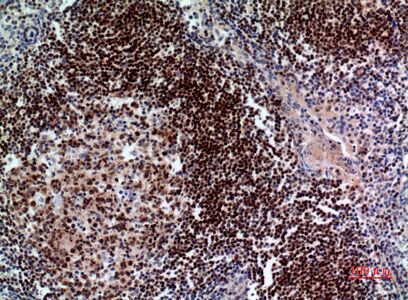

Immunohistochemical analysis of paraffin-embedded human-tonsil, antibody was diluted at 1:100